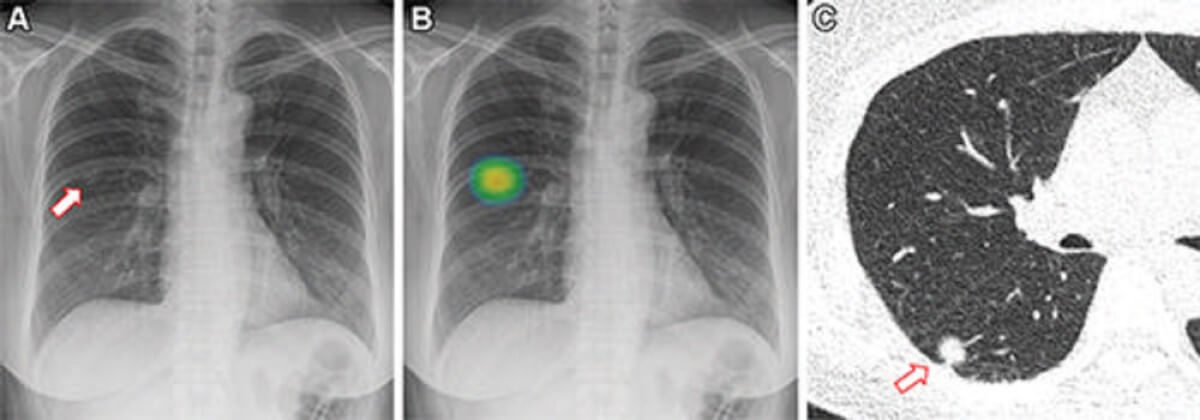

Εικόνες μιας 60χρονης γυναίκας που υποβλήθηκε σε ακτινογραφία θώρακος και ελέγχθηκε από το σύστημα τεχνητής νοημοσύνης (ΤΝ). (Α) Η μετωπική ακτινογραφία θώρακος δείχνει μια ανεπαίσθητη οζώδη αδιαφάνεια (βέλος) στη δεξιά μεσαία ζώνη του πνεύμονα. (Β) Η βλάβη ανιχνεύθηκε από το λογισμικό ανίχνευσης με τη βοήθεια ΤΝ, με πιθανότητα ανωμαλίας 81,1%. Ο άνθρωπος ακτινολόγος ανέφερε αυτήν την ακτινογραφία θώρακος ως θετική. (Γ) Η αξονική τομογραφία θώρακος χαμηλής δόσης χωρίς σκιαγραφικό δείχνει ένα συμπαγές οζίδιο (βέλος) 1,1 cm στον κάτω δεξιό λοβό. Η ασθενής υποβλήθηκε σε διαδερμική βιοψία με βελόνα και επιβεβαιώθηκε ότι ο όζος ήταν αδενοκαρκίνωμα.